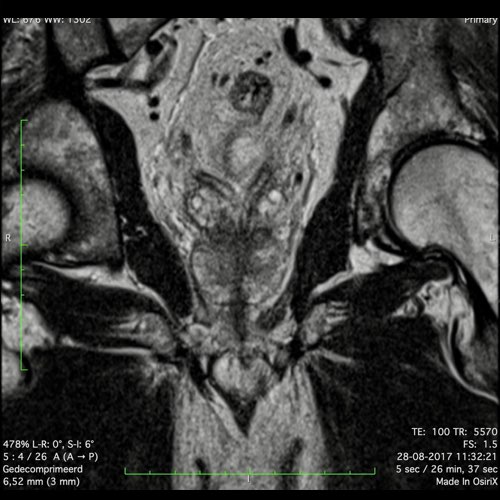

Hình ảnh

Các hình ảnh được cung cấp cho thấy ung thư biểu mô tế bào nhẫn với tình trạng dày lan tỏa thành trực tràng, hình ảnh bia bắn điển hình, và sự xâm lấn mỡ mạc treo trực tràng.